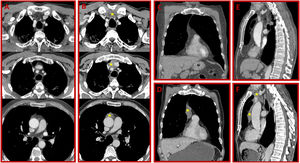

A 58-year-old man presented for evaluation of the right preauricular mass. Head, neck and thorax computed tomography (CT) scan showed an infiltrative neoplasm of the right parotid gland. In thorax CT, there were pleuroparenchymal band formations. Mediastinum organs were completely normal (Fig. 1A, C, and E). No distant metastasis was demonstrated in positron emission tomography (PET)-CT. The patient was treated surgically. He did not receive chemotherapy. Histopathologic examination revealed parotid gland carcinoma. After three months, control CT and PET-CT showed rebound thymic hyperplasia in the anterior mediastinum (Fig. 1B, D, and F) without increased FDG uptake. There was any metastatic focus in PET-CT scans.